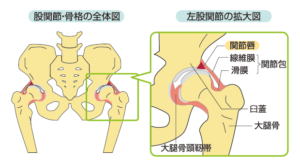

大腿骨の頭、つまり大腿骨は、骨盤の受け皿にフィットするボールのような形をしています。関節唇は、ソケットの端に沿った軟骨の輪で、股関節に安定性を与え、衝撃を吸収するのに役立ちます。

唇裂傷はこの軟骨の裂傷です。股関節を動かすときに痛み、不安定性、カクカク音が発生することがあります。